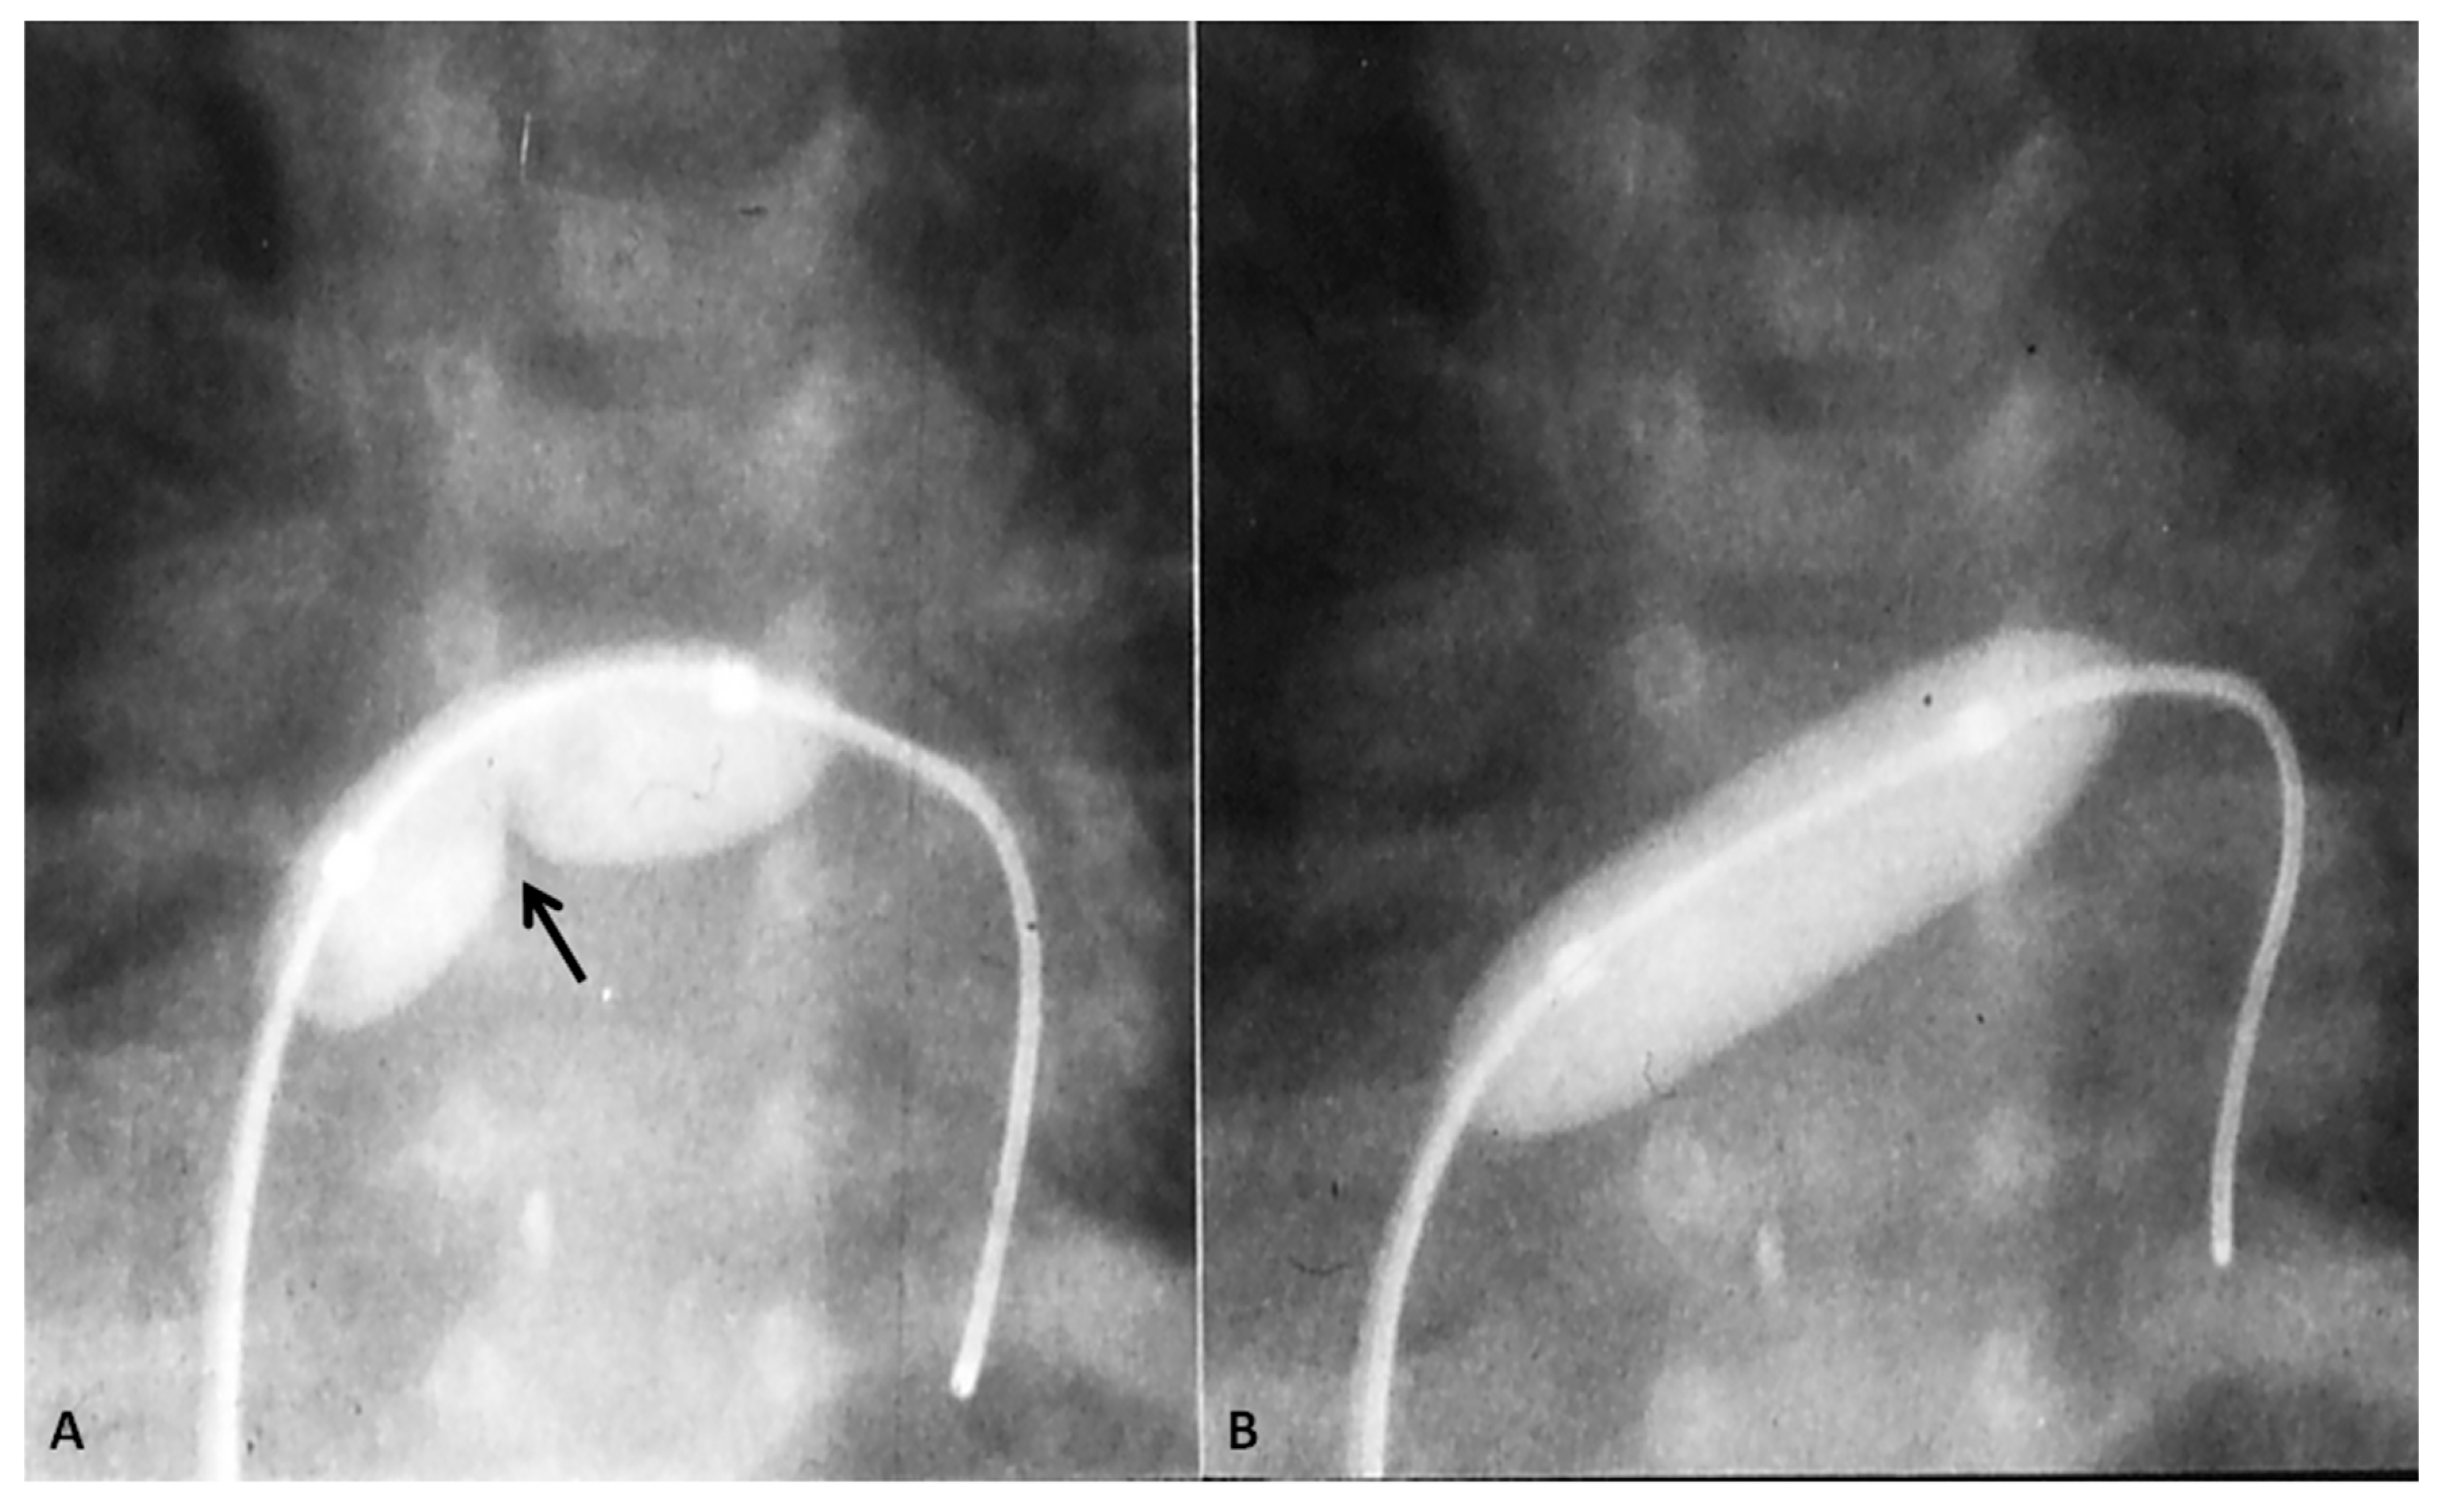

7.3.3. Ensure Adequate Egress of the Left Atrial Blood

The left atrial blood must egress into the right atrium, across the PFO, because of the obstructed mitral valve/LV. In some infants, the PFO may be small at birth or may become restrictive with time. Mild degree of narrowing may be beneficial in that it will increase the PVR which in turn may help adequate systemic flow. However, severe restriction produces pulmonary edema with consequent hypoxemia. Consequently, it is important to perform periodic echo-Doppler studies in order to monitor the size of the PFO and the degree of restriction. When the obstruction becomes severe, enlargement of the PFO by trans-catheter techniques [41,42,43,70] should be performed. While Rashkind’s balloon atrial septostomy [41] and Park’s blade septostomy [43,70] are conventional methods to lessen atrial septal obstruction, such techniques are not easy to perform because of the hypoplastic left atrium. Static balloon dilatation of the atrial septum [42,102,103] with a balloon angioplasty catheter (Figure 12) is useful. Such a procedure may not only help relieve severe obstruction, but also retain a mild degree of obstruction so that rapid fall in the PVR does not occur. Rarely, the obstruction is extremely severe and may require stent implantation [42,104].